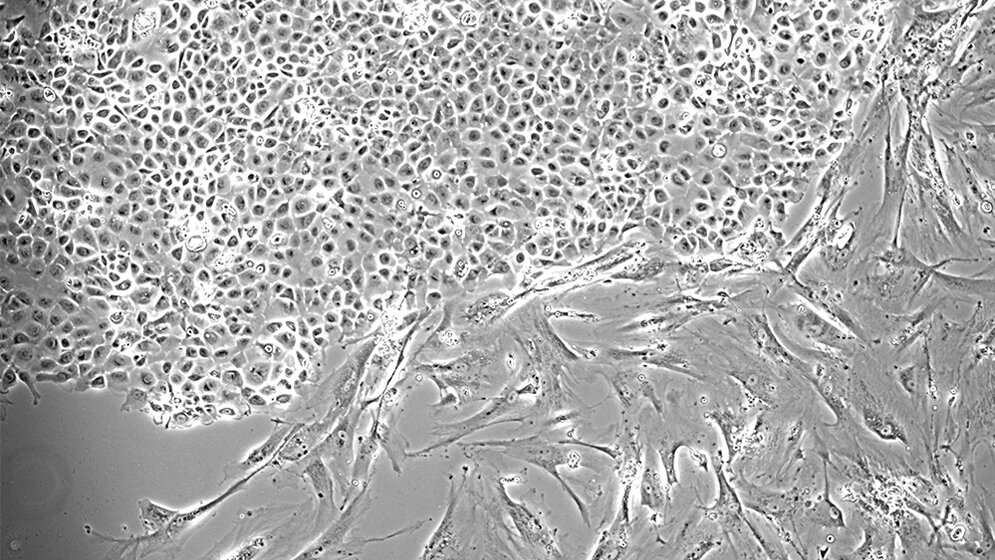

Stathopoulos und sein Team arbeiten daran, die unklaren Ursachen für den Pleuraerguss zu verstehen, um künftig dagegen vorzugehen. In der aktuellen Studie untersuchten die Wissenschaftler Krebszellen mit einer bösartigen Mutation im KRAS-Gen, die sie aus Pleuraergüssen gewonnen hatten. KRAS ist bekannt dafür, eine entscheidende Rolle für das Wachstum verschiedener bösartiger Tumoren zu besitzen.

„Wir konnten zeigen, dass diese Zellen einen Botenstoff ins Blut abgeben, der wiederum Immunzellen anlockt.* Diese wandern dann über die Milz in die Pleurahöhle ein und verursachen dort die Flüssigkeitsansammlung“, erklärt Studienleiter Stathopoulos den Mechanismus. Zusätzlich fanden die Wissenschaftler die KRAS mutierten Krebszellen in MPE-Material von Lungenkrebspatienten sowie in Zelllinien, die davon abgeleitet worden waren.